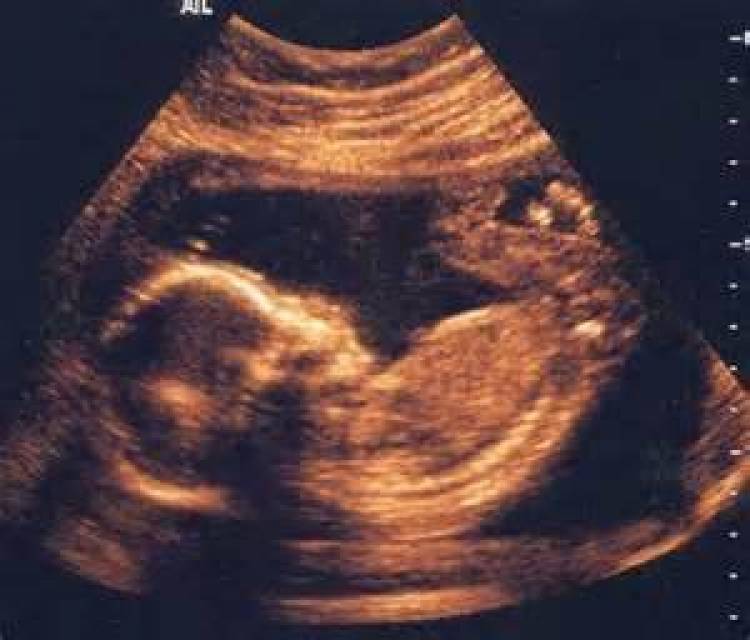

Είκοσι χρόνια μετά την πρώτη επιστημονική δημοσίευση, η Αυχενική Διαφάνεια, εξέταση υπερήχων που πραγματοποιείται μεταξύ 11ης και 14ης εβδομάδας της κύησης, είναι η σημαντικότερη εξέταση προγενετικής διάγνωσης τόσο του συνδρόμου Down όσο και άλλων ανωμαλιών του εμβρύου.

Χάρη στη συγκεκριμένη εξέταση, όχι μόνον μειώθηκε ο αριθμός των γυναικών που υποβάλλονται σε αμνιοπαρακέντηση –με κίνδυνο αποβολής– αλλά υπάρχει δυνατότητα να ανιχνευθούν περισσότερες περιπτώσεις συνδρόμου Down. Μέσω της Αυχενικής Διαφάνειας που γίνεται σε όλες τις γυναίκες εντοπίζονται οι κυήσεις υψηλού κινδύνου και σε αυτές γίνεται αμνιοπαρακέντηση, ανεξάρτητα από την ηλικία. «Με τον τρόπο αυτό οι αμνιοπαρακεντήσεις στην Αγγλία φέτος θα πέσουν κάτω από το 2%-3%. Στην Ελλάδα το ποσοστό των γυναικών που υποβάλλονται σε αμνιοπαρακέντηση είναι 25%-30%. Είτε οι γυναίκες είναι νευρωτικές είτε οι γιατροί χρειάζονται παραπάνω εισοδήματα...».

Η Αυχενική Διαφάνεια «δείχνει» και άλλα προβλήματα, δίνοντας δυνατότητα να εκτιμηθεί η πορεία της εγκυμοσύνης. «Πολλά πράγματα μπορείς να δεις από τη 12η εβδομάδα της κύησης. Προτείνω, λοιπόν, να αναποδογυρίσουμε το μοντέλο της πυραμίδας της προγενετικής παρακολούθησης από το τέλος στα αρχικά στάδια της εγκυμοσύνης, προβλέποντας ποιες γυναίκες έχουν σοβαρό κίνδυνο να έχουν επιπλοκές ώστε να λάβουμε μέτρα».